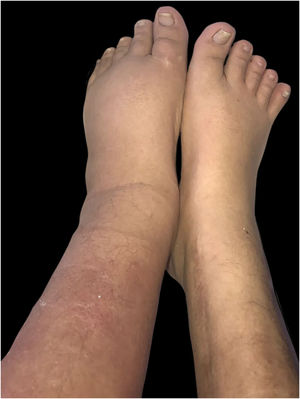

Durante a internação por bacteremia secundária à infecção do trato urinário, foram observadas placas eritematosas com bordas difusas e discreta descamação superficial assintomáticas na superfície anterior e lateral da perna esquerda (figs. 1 e 2).

A infecção por Prototheca varia de envolvimento indolente e localizado da pele, infecção de tecidos moles, bursite do olecrano em pacientes imunocompetentes, a infecção disseminada devastadora com algemia e infiltração visceral com alta mortalidade em hospedeiros imunocomprometidos em decorrência de transplante, diabetes, HIV e doenças hematológicas.2,3 A forma cutânea representa a manifestação mais frequente (três em quatro pacientes). As lesões geralmente aparecem em áreas expostas à implantação traumática. Em geral, apresenta‐se como placas eritematosas mal definidas, embora com menos frequência possa se manifestar como lesões nodulares, pustulosas, verrucosas e ulceradas.